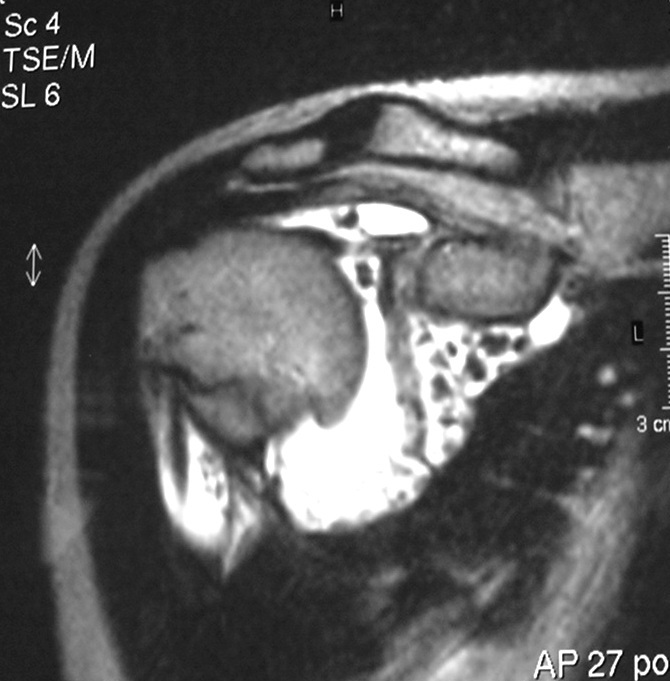

Synovial chondromatosis is an uncommon, benign, process that occurs in large joints, such as the knee (50%), hip, elbow, or shoulder. This process mainly affects synovium and hence most commonly arises from joints and tendons which are lined by synovium. Synovial Chondromatosis may also affect bursae and extend into surrounding soft tissues. This condition is seen in patients between 20 and 50 years of age and most commonly in men (male-female ratio of 2-4/1). The patient usually complains of pain, stiffness, crepitance, swelling, and joint locking. The knee is the most common site to be affected. Symptoms are long-standing and progressive. The plain x-ray may be normal (5 to 33%) or there may be small flecks of calcification (Fig. 1 & 2). On MRI the nodules of cartilage are easily seen. MR imaging may also show synovial thickening, joint erosions and intraarticular calcifications. The signal characteristics of these intraarticular bodies depend of their composition. If mineralization is not present the signal intensity follows the cartilage signal with intermediate signal on T1 images and high signal on T2 weighted MR images. Uniformly calcified bodies follows bone density on all sequences with bone marrow signal centrally and low signal peripherally (Fig. 3-5). Histologically the cartilage is arranged in nodules, which are quite cellular (Fig. 7-9). Synovial lining is present surrounding the cartilage nodules (Fig. 8). The cartilage nodules are often referred to as loose bodies however they are not really loose and embedded in the synovium lining. This is considered a metaplastic condition as opposed to a true neoplastic condition. Rarely it may turn into a malignancy usually a low grade chondrosarcoma. Malignant change is suggested by deep erosions into adjacent bone.

Fig. 4 & 5. MR images of the right shoulder. Axial (Fig. 4) and coronal (Fig. 5) T2-weighted images demonstrate high signal in the right shoulder corresponding with proliferation and swelling of the synovium. Multiple bodies with low signal that follow bone density in all sequences.